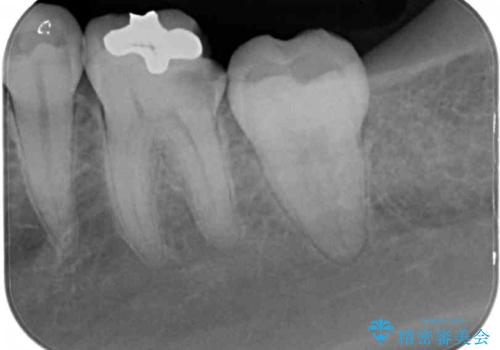

痛みなどは特になく、診査をしたところ歯の神経に大きな問題はなかったのですが、レントゲン写真より神経に近くに迫るほど大きなむし歯があることが分かりました。

虫歯が歯髄腔(神経の部屋)に達している可能性が非常に高かったため、炎症を起こしている神経組織を部分的に切除し、歯根部分の神経組織を保存する治療法が望ましいと考えられました。